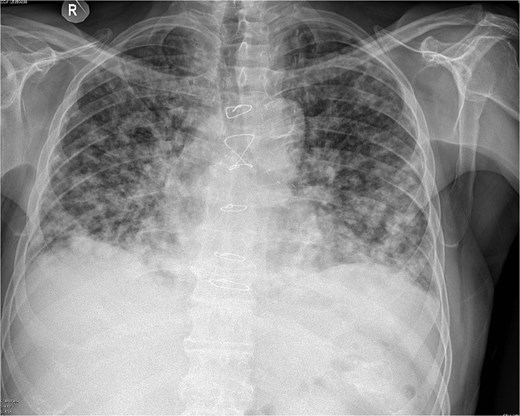

Due to improvement in his symptoms, the patient did not attend his three-month follow-up appointment. Eight months later, the patient was hospitalized with shortness of breath and multiple pulmonary nodules (Fig. 1) on the chest computed tomography (CT) in the pulmonology department of our hospital. Figures 2 and 3 show the preoperative chest X-ray and the chest X-ray taken eight months after the TURP, respectively. Suspected of metastatic disease, a urological evaluation was performed, which revealed an abnormal DRE and a significantly elevated PSA of 134 ng/ml. Diagnostic bronchoscopy and histological findings of the lung biopsy confirmed prostate adenocarcinoma (PCa). TRUS-Bx prostate biopsy (12 cores) confirmed the diagnosis of PCa with involvement of all prostatic cores and Gleason Score (GS) = 8 (4 + 4). Bone scan (Fig. 4) and CT scan were negative for other secondary metastatic lesions in bones and lymph nodes. The patient immediately started combination therapy ADT (degarelix) with apalutamide, and 3 months later, he was off oxygen, and his PSA level had decreased to 14.9 ng/ml.